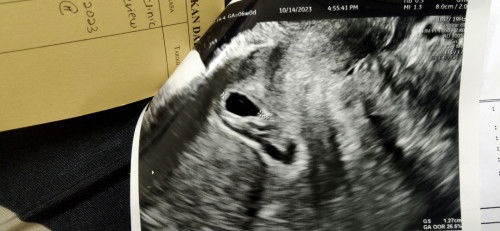

sy dh pergi scan dkt hosp..sbb sy bleeding smpai ke harini , darah takbanyak keluar ,tp die berdarah..and dctr scan dkt bwh die ckp kantung cantik, cumanya janin duk di bawah..sbb tu katanya sy bleeding, tp bleeding sy xd kluar darah ketul2 daging atau apa apa..so dctr decide bg mase kt sy 3w untuk janin turun sndri..kalau tak sy kena buat DNC😭😭😭 tp dctr takckp details pun psl kandungan sy, sy plak yg byk bertanya.dala time tu tgh sedih takmmpu nk brkata apa2.. kandungan sy baru masuk 6w2d#pleasehelp #seriusnanya #ingintahu #bantusharing